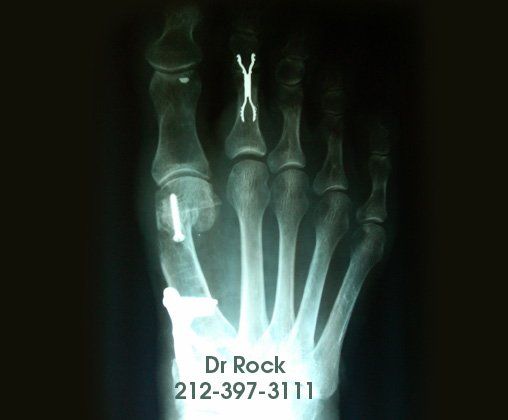

Get Beautiful, Pain-Free Feet

Take a look at our x-ray pictures of our recent footwork and see how your feet can benefit.

Whether you want to improve the look of your feet or need to relieve pain,

you can find out the best option for you with our FREE phone consultation.